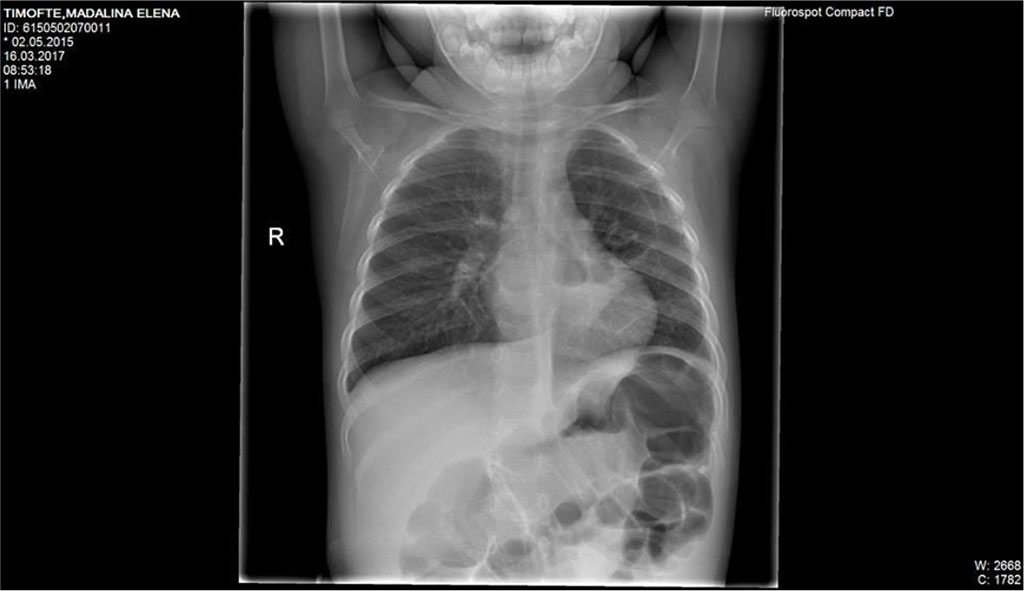

Blood test showed an increased number of leukocytes (37170/mmc) with predominance of neutrophils (92%) and an important inflammatory syndrome (CRP=252mg/l). Chest x-ray at the onset showed an opacity located on the upper right pulmonary lobe and presence of fluid in the right costo-diafragmatic sinus (Fig.4).

Fig.3 Mild interstital infiltrate of both lungs; pulmonary two radiotransparent lesions that appear near hearth

Fig. 4. Opacity located on the upper right pulmonary lobe and presence of fluid in the right costo-diafragmatic sinus